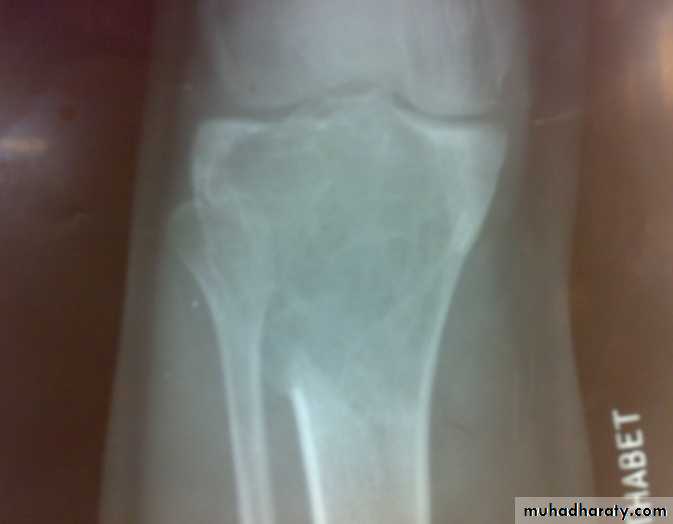

Giant cell tumor

Patient presented by local pain and swelling or pathological fractures. Common site is the distal femur, proximal tibia, distal radius.

X-ray show eccentric osteolytic lesion in the end of long bone ,subchondral, trabeculated (soap bubble appearance). The cortex is thin, expanded or even perforated.